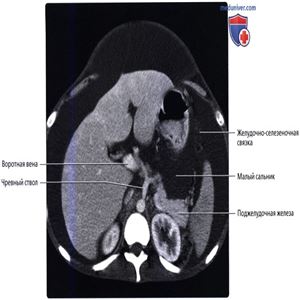

Сальниковая сумка и брюшинная полость расширены асцитической жидкостью. Желудочно-селезеночная связка и поджелудочная железа образуют границу сальниковой сумки, как и малый сальник, положение которого обозначается воротной веной и чревным стволом.

Малый сальник и желудочно-селезеночная связка образуют две из стенок сальниковой сумки. Малый сальник на этом изображении можно идентифицировать по расположению воротной вены и печеночной артерии.